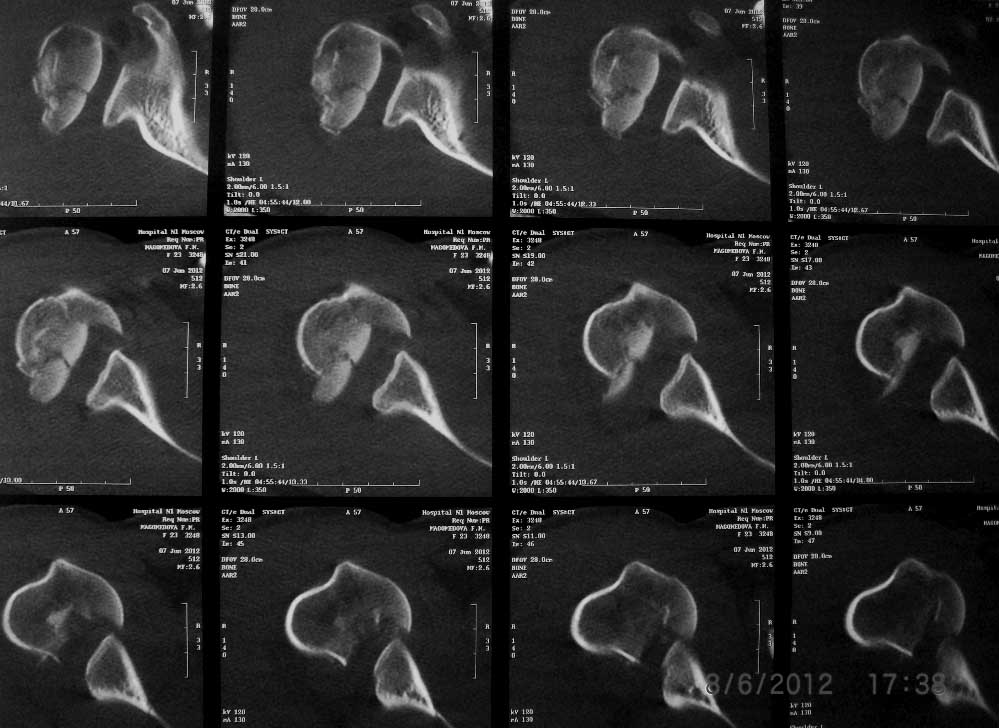

Женщина 23 лет получила травму в результате ДТП (пассажир). Поступила в отделение 07.06.2012 (травма в день поступления).

Диагноз: закрытый перелом шейки правого плеча с отрывом большого бугорка, закрытый поперечный оскольчатый перелом правого плеча на границе средней и нижней трети.При поступлении конечность иммобилизирована задней гипсовой лонгетой от надплечья до головок пястных костей.

Вложение не в текстовом формате было извлечено…

Имя     : ct.JPG

Тип     : image/jpg

Размер  : 108928 байтов

Описание: отсутствует

Url     : http://weborto.net:8080/pipermail/ortho/attachments/20120609/f6e7d42f/attachment-0003.jpg